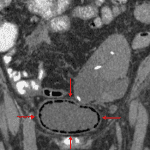

- Curvilinear lucencies outlining the urinary bladder

- Emphysematous cystitis

Curvilinear lucencies outlining the urinary bladder, which raises concern for emphysematous cystitis. Recommend correlation with urinalysis and CT for further evaluation.